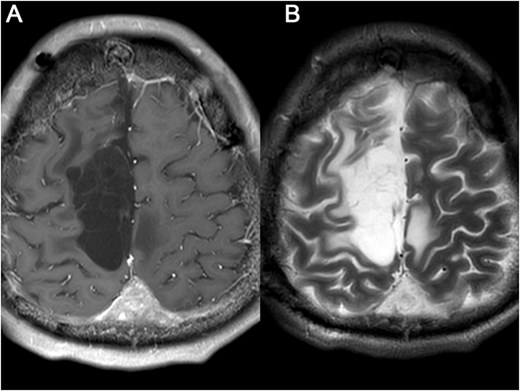

A 23-year-old male presented to our hospital with a 3-day history of episodic left upper limb paralysis. Upon admission, he reported progressive left lower limb motor incoordination, temporal visual field defects in the left eye, bilateral vision,deterioration, and bilateral olfactory hypesthesia over the preceding 3 months. Three days prior to admission, he experienced sudden-onset left upper limb paralysis lasting ~10 minutes before spontaneous resolution. Cranial magnetic resonance imaging (MRI) revealed a giant meningioma (>8 cm in diameter) causing extensive compression of adjacent structures, with marked heterogeneous enhancement on contrast imaging (Fig. 1). Preoperative intracranial vascular embolization was performed, followed by tumor resection via a bifrontal-parietal approach 1 day later (Fig. 2). Intraoperative findings confirmed a tumor >8 cm in diameter with cranial bone erosion (Fig. 3). Postoperatively, the patient developed transient bilateral lower limb paralysis (muscle strength grade 0) on Day 1, which resolved completely within one month. Histopathological analysis demonstrated features consistent with atypical meningioma: sheet-like growth pattern, increased nuclear-to-cytoplasmic ratio, prominent nucleoli, focal necrosis, and immunohistochemical staining showing Vimentin(+), SSTR2(+), PR(+), EMA(−), and a Ki-67 proliferation index of 5%–10%. The patient underwent gamma knife radiosurgery at 6 months and 1 year postoperatively. Three-year follow-up MRI showed no tumor recurrence or significant progression of residual lesions (Fig. 4), with significant improvement in visual acuity, hearing, and visual field deficits.

Preoperative MRI: (A, B) axial post-contrast T2-weighted and T1-weighted, respectively (C, D) sagittal position post-contrast T2-weighted and T1-weighted, respectively. The MRI findings describe a lesion in the right frontoparietal region adjacent to the superior sagittal sinus, measuring ~8.6 × 8.2 × 6.9 cm. The lesion demonstrates long T1 and T2 signal characteristics and exhibits marked heterogeneous enhancement on contrast-enhanced scans. It encircles the superior sagittal sinus and extends across the cerebral falx to the contralateral side, with multiple tortuous flow-void vascular shadows observed within and around the lesion. The mass is broadly attached to the adjacent calvarium, invading the diploic layer of the skull. Posteriorly, it extends along the superior sagittal sinus to the origin of the left transverse sinus. Compression of adjacent brain parenchyma results in irregular narrowing of the lateral ventricle and leftward shift of midline structures. Additionally, the cerebellar tonsils appear pointed and inferiorly displaced.